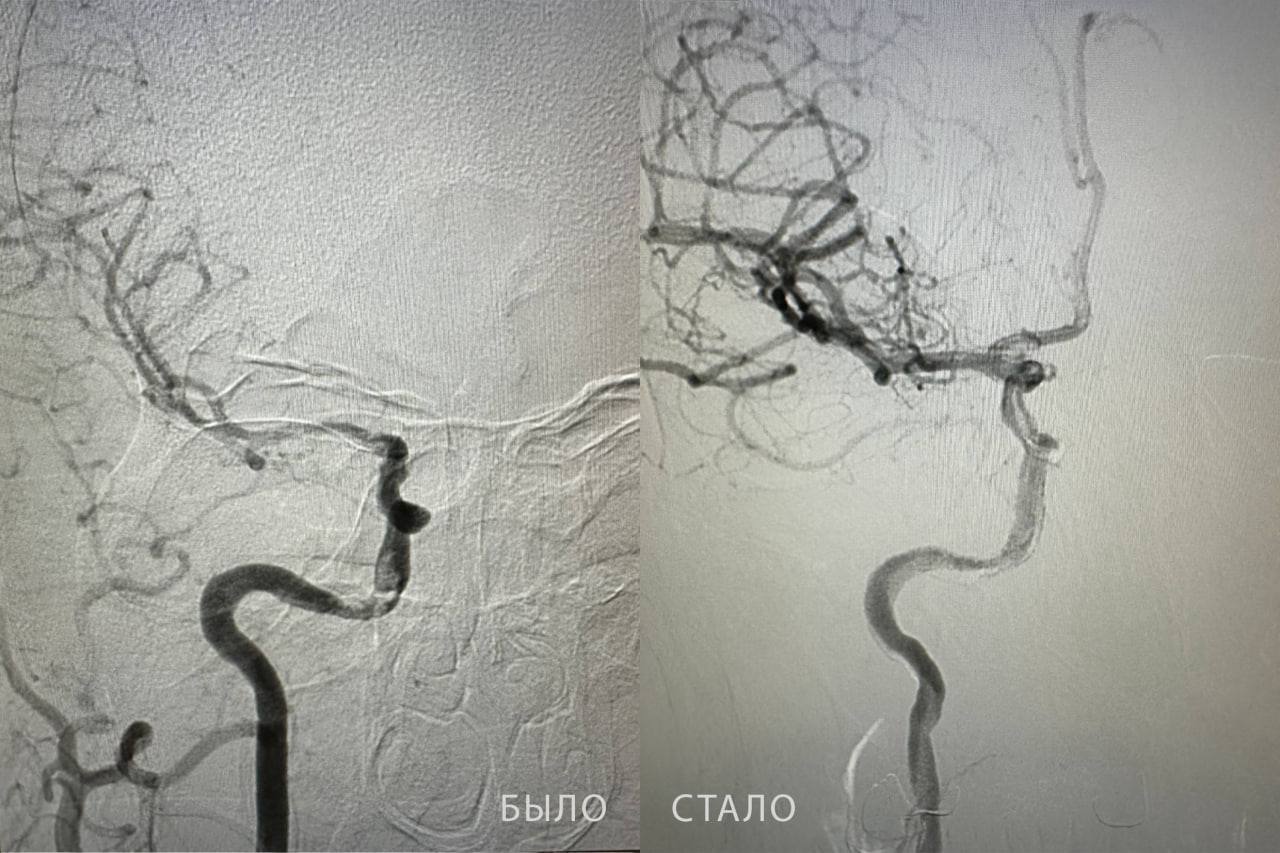

Ангиохирург Бакназар Абдыкадыров провел сложную операцию и успешно извлек тромб длиной почти 2 сантиметра. Кровоток восстановился, и благодаря слаженной работе медиков пациент вернулся к полноценной жизни. У него восстановились речь, симметрия лица и двигательная активность.